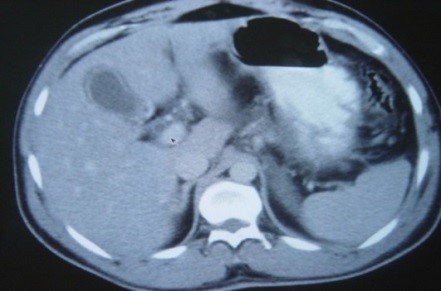

- Zədələnmələrin olub-olmamasını, yеrini və xaraktеrini dəqiqləşdirmək üçün xolangioqrafiya еdilir. MRT ilk seçimdir, lakin dəqiqləşdirmə üçün adətən kontrastlı xolangioqrafiya edilir: əməliyyat vaxtı əməliyyatdaxili xolangioqrafiya, əməliyyatdan sonra isə endoskopik və ya perkutan xolangioqrafiya.

- Öd yollarına yeridilən kontrastın kənara çıxması və ya “blok” (bağlanma) zədələnməni təsdiqləyən əlamətləridir.

Diaqnostik əlamətlər:

- Biliar sızıntı (peritonit, fistul, bilioma, qaraciyərdaxili abseslər) və / və ya mexaniki sarılıq

- Xolangioqrafiyada biliar ekstravazasiya və ya blok

Əməliyyatdan sonra tapılan bağlamalarda xəstə ixtisaslaşmış klinikaya göndərilir. Belə xəstələrdə ilk olaraq MRT edilərək bağlanma yeri dəqiqləşdirilir. MRT yetərsiz olarsa ERXPQ edilə bilər. Əlavə olaraq KT angioqrafiya və ya dopler USM ilə arteriya zədələnməsini yoxlamaq lazımdır. Diaqnostik işləmlərdən sonra zədələnmə yerinə və ağırlaşmalara görə müalicə taktikası seçilir. Magistral axacaqların bağlanmasında xəstə nəzarət altında saxlanılır, anastomoz üçün 2-3 həftə gözlənilir və ağırlaşmaların profilaktikası həyata keçirilir. Bu müddət öd yollarının genişlənməsi, divarının qalınlaşması, iltihabın sönməsi və anastomoz üçün əlverişli şərait yaratmaq məqsədi daşıyır. Gözləmə müddətində ağırlaşmaların profilaktikası və müalicəsi üçün aşağıdakı tədbirlər həyata keçirilir: